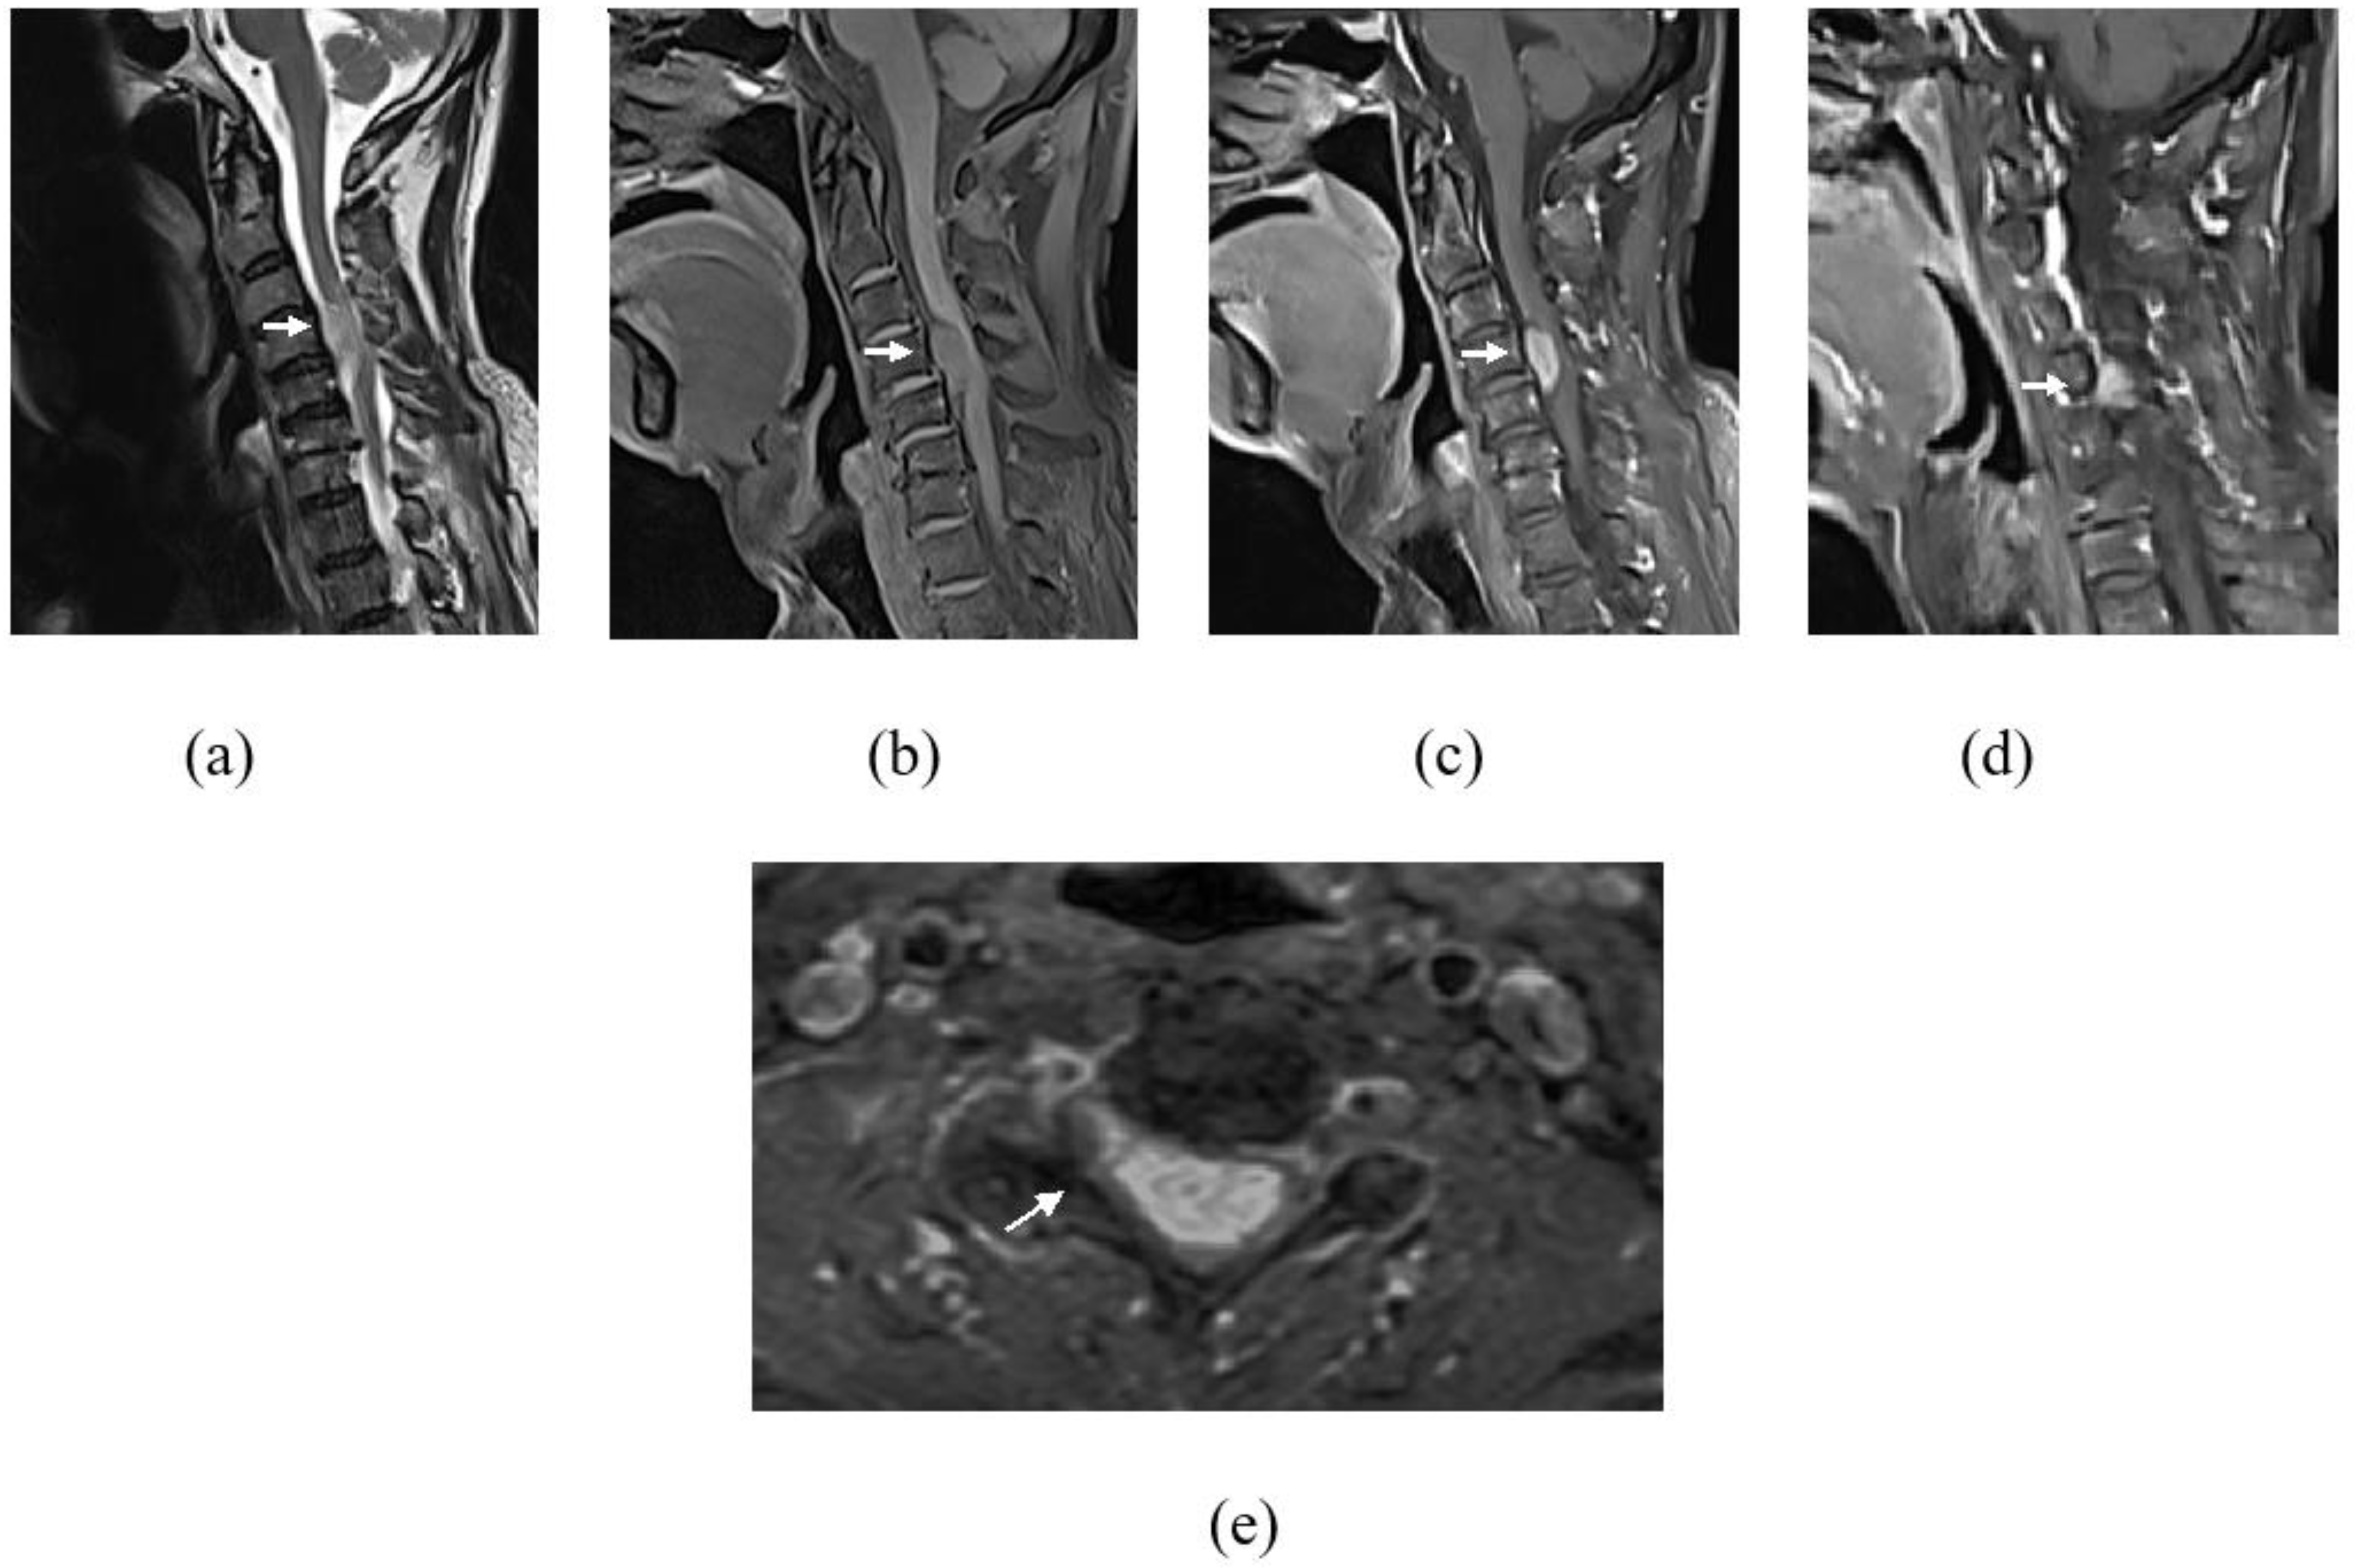

Figure 2.

Images of cervical spine showing an intradural extramedullary lesion (white arrow) at the level of C4–C5. It demonstrates hyperintense signal on T2WI (a), intermediate signal on T1WI (b) and avid enhancement on gadolinum-T1FS sequence (c,e). This lesion causes spinal cord compression at this level with associated spinal cord T2WI hyperintense signal indicating of cord oedema (a). Right parasagittal image (d) showed extension into the right C4 neural foramina (e).